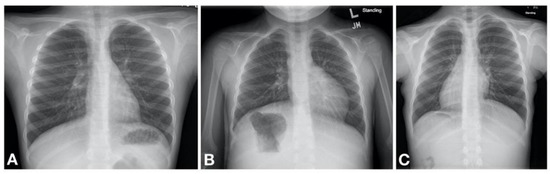

Figure 2. Machogu et al. Laterality defects found on chest radiography of patients with PCD. (A) Normal; Left sided cardiac apex with left sided stomach and right sided liver (B) Situs Ambiguous; Left sided cardiac apex with right sided stomach and left sided liver (C) Situs Inversus Totalis; right sided cardiac apex with right sided stomach and left sided liver.

The abnormal function of motile cilia results in impaired mucociliary clearance from the respiratory system and stagnation of purulent mucus that inevitably leads to recurrent and chronic oto-sino-pulmonary infections [12]. The PCD clinical phenotype is heterogenous and disease progression is likely related to the associated gene mutations [13]. Nonetheless, nearly all patients with PCD have early onset, year round wet and productive cough, while about 80% have early onset, year round daily nasal congestion and chronic sinusitis [14]. Recurrent bronchitis and pneumonia ultimately leads to development of bronchiectasis [15]. Additional clinical features include situs inversus totalis (SIT) in about half of the patients [12] while about 12% are reported to have other forms of heterotaxy [16] (Figure 2). Infertility is present in nearly all male patients due to reduced motility of spermatozoa [12]. Table 1 summarizes the clinical manifestations of PCD.